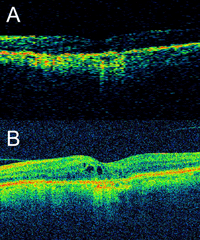

Figura 1).

Figura 1. Diferencia en resolución de imágenes de OCT de dominio tiempo y espectral. (A) Imagen con OCT de dominio tiempo (Stratus OCT-3, Carl Zeiss Meditec, Dublin, CA, USA). (B) Mismo ojo escaneado a continuación con OCT de dominio espectral (Cirrus HD-OCT, Carl Zeiss Meditec, Dublin, CA, USA). La mayor velocidad de escaneo con el dispositivo de dominio espectral permite obtener una mayor cantidad de scans en modo A en una única captura, que a continuación son promediados por el software integrado en el dispositivo permitiendo obtener imágenes de una mayor resolución. Esto hace posible analizar detalles con precisión, como estos quistes intraretinianos no detectados en la imagen obtenida con el dispositivo de dominio tiempo. Además, esta mayor velocidad de escaneo hace que sea posible cubrir áreas más amplias en prácticamente el mismo tiempo de captura, disminuyendo el riesgo de pasar por alto detalles focales no capturados en scans lineales únicos.